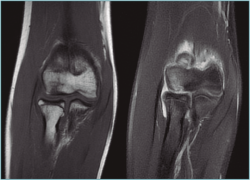

La tomografía computarizada (TC) permite una mejor definición del defecto. La resonancia magnética (RM) muestra edema óseo en las fases más iniciales(1). Además, esta última permite medir el tamaño y la extensión del defecto articular, que es esencial para planificar el tratamiento. En fases iniciales, se aprecian cambios en las secuencias T1 con aspecto normal en T2 (Figura 2). Cuando comienza a fragmentarse, se origina una señal hiperintensa alrededor de la lesión detectable en la secuencia T2, signo demostrativo de inestabilidad. Jans et al.(8) determinaron que la RM tiene una sensibilidad del 100% para diagnosticar una lesión inestable. Además, es extremadamente efectiva para localizar cuerpos libres, que aparecen en el 36% de los casos y que se calcifican con el tiempo, localizándose en la cámara anterior o la gotiera lateral (Figura 3).

Figura 2. Imágenes de resonancia magnética en el plano coronal del codo, donde se aprecia una lesión osteocondral en el capitellum con señal hiperintensa en la secuencia T2 (imagen derecha).